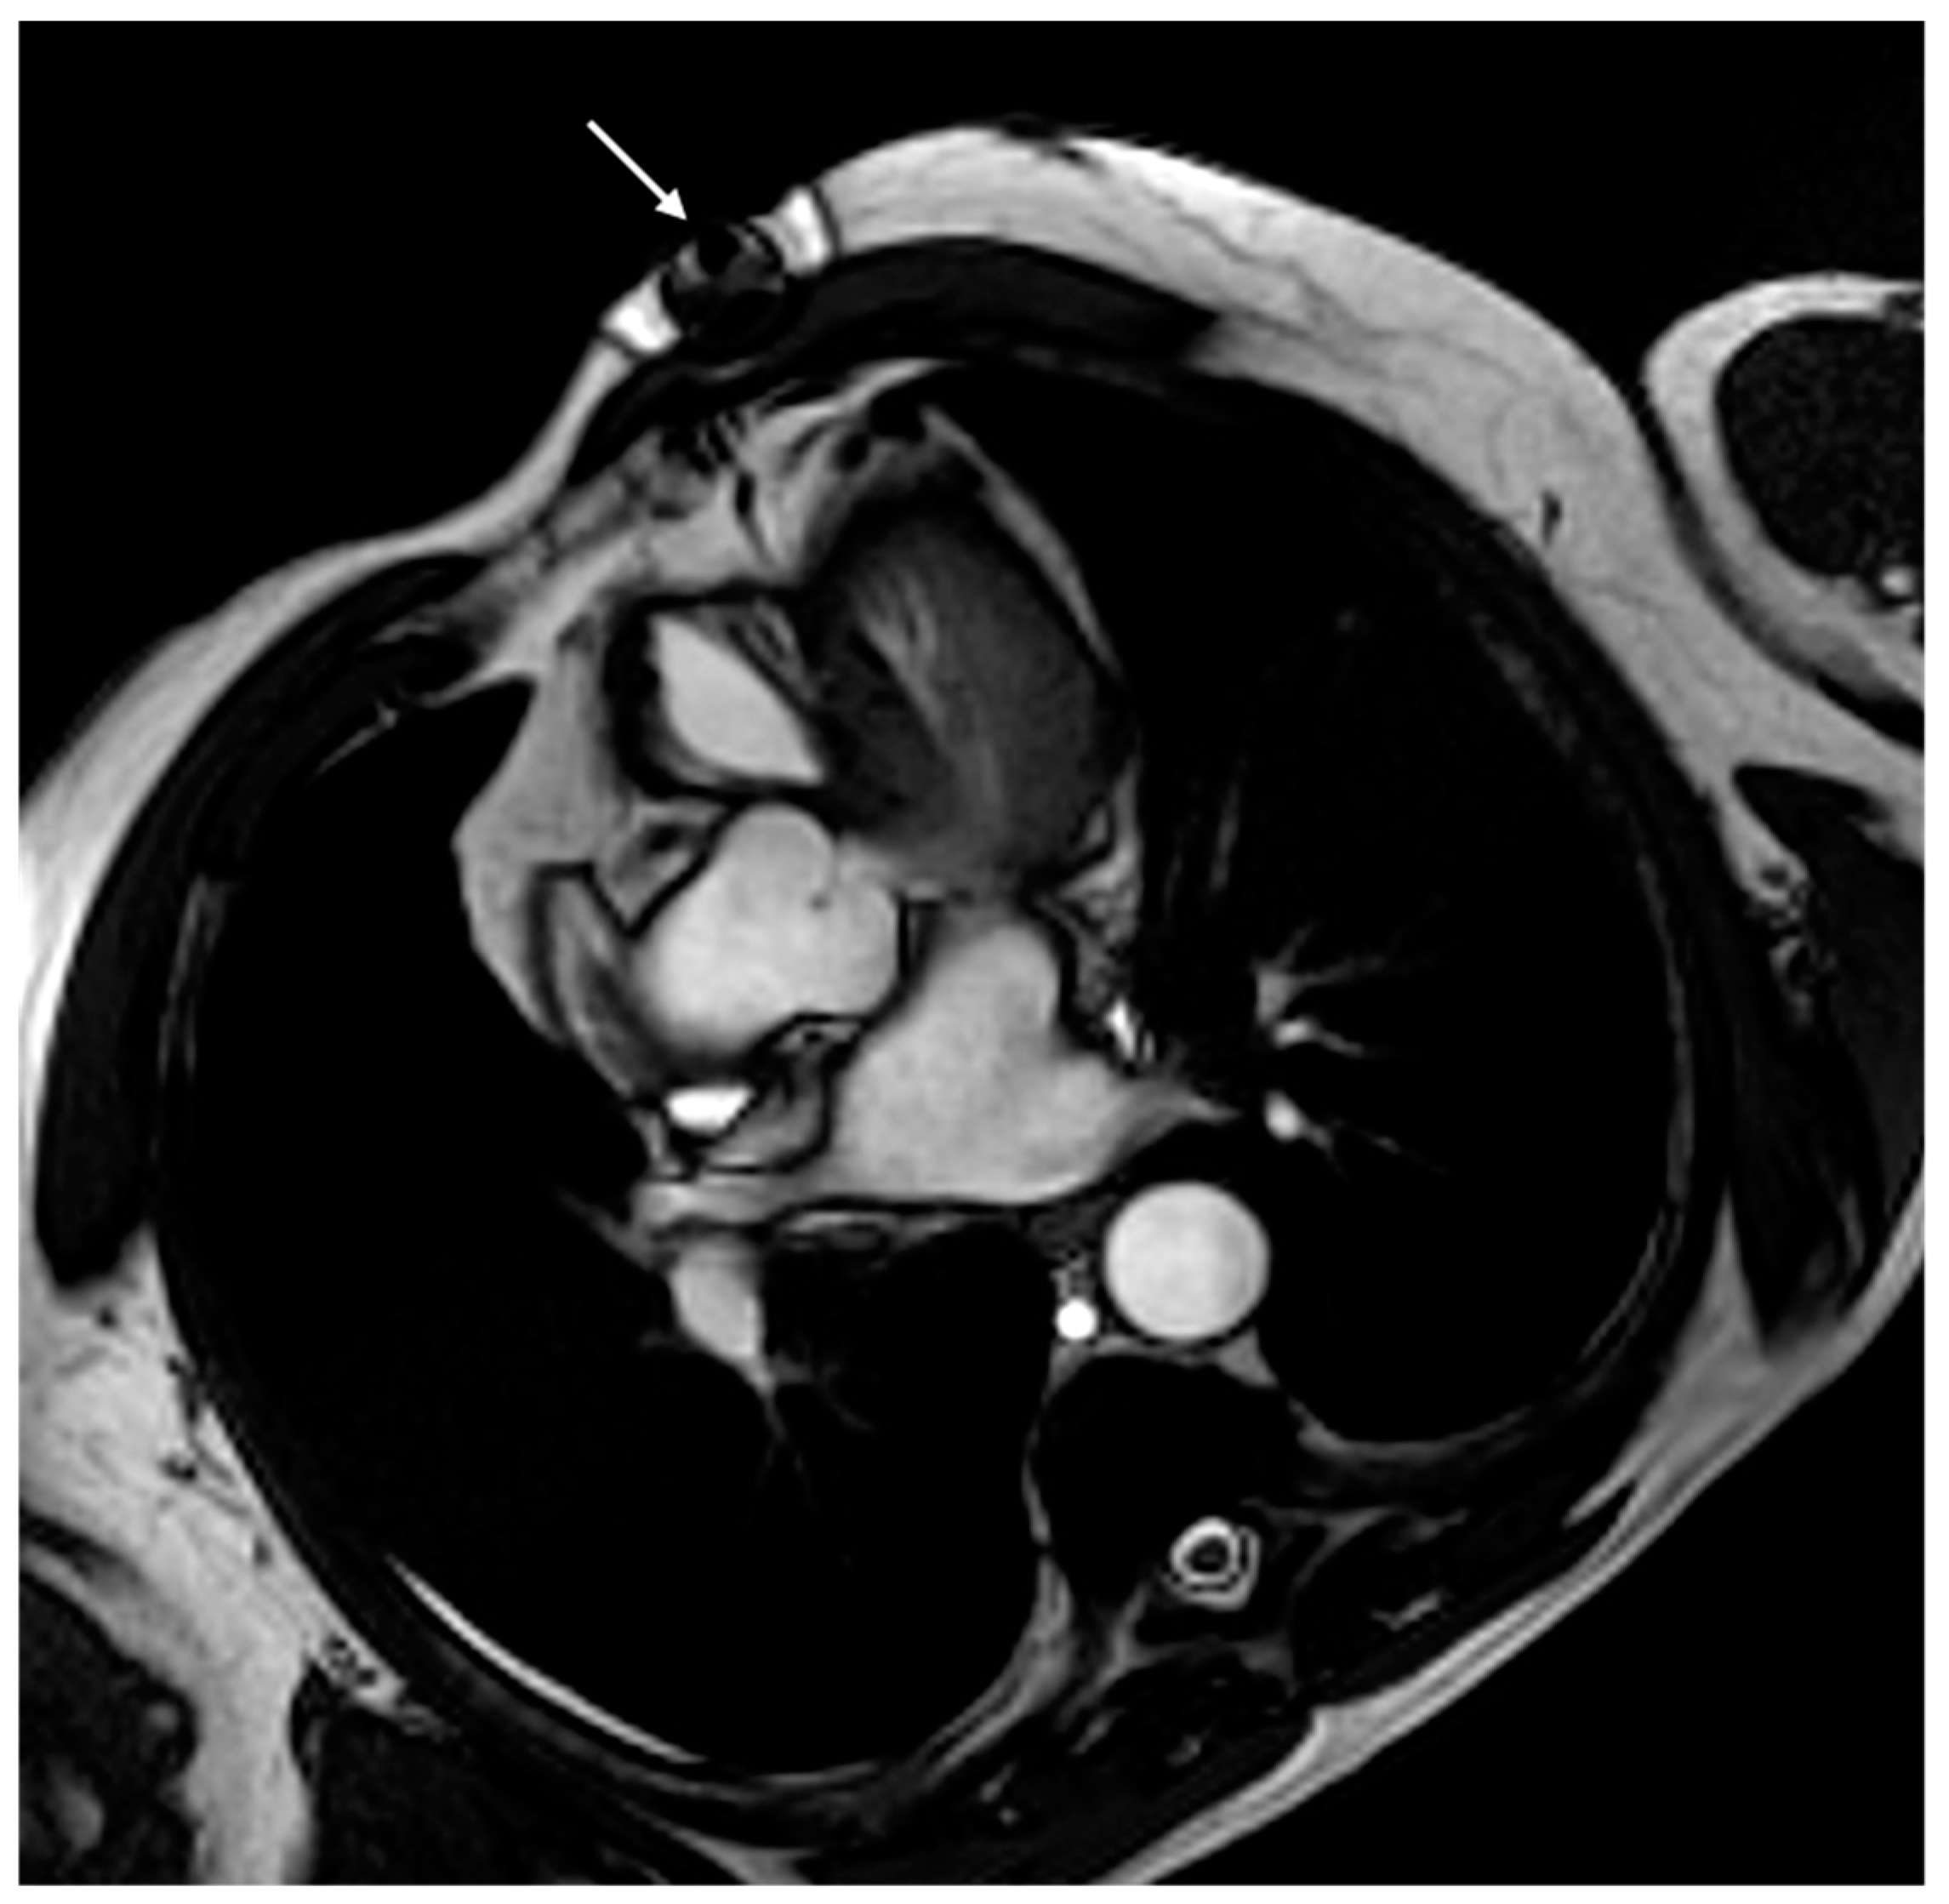

6. Issue: Artifact